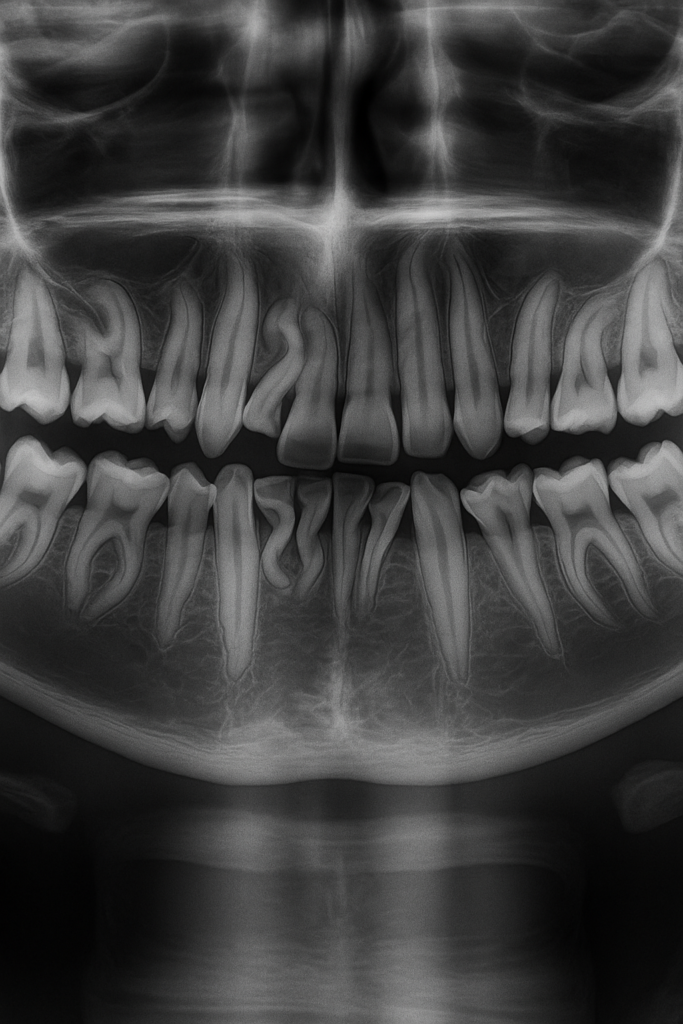

✅ Evaluación precisa con diagnóstico por imágenes

Evaluamos cada caso con imágenes diagnósticas de alta precisión.

Tecnología de diagnóstico 3D y radiografías digitales

Planificamos cada procedimiento con máxima precisión.